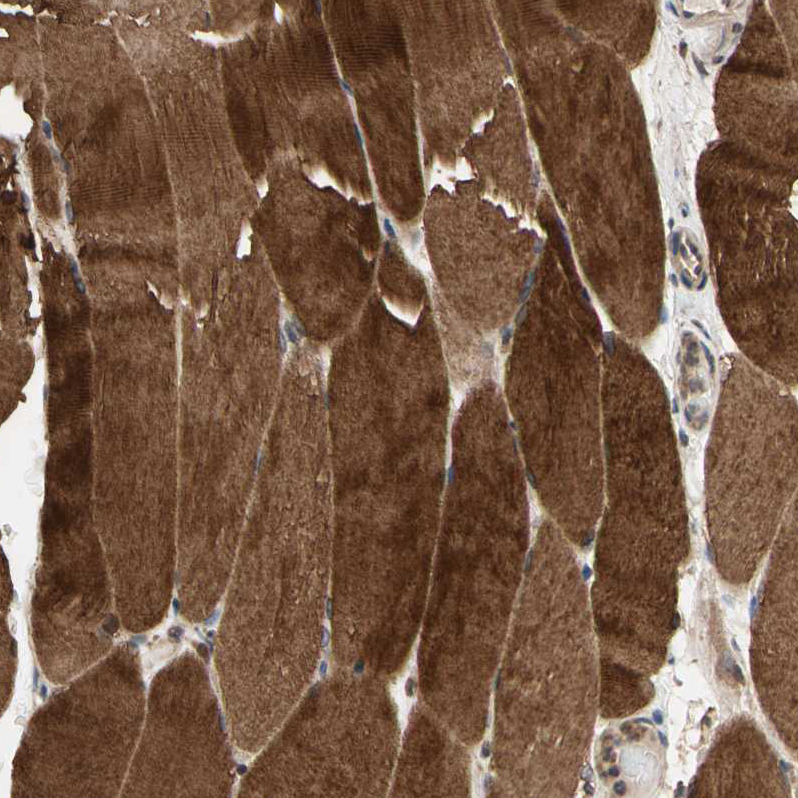

Immunohistochemical staining of human skeletal muscle shows strong cytoplasmic positivity in myocytes.